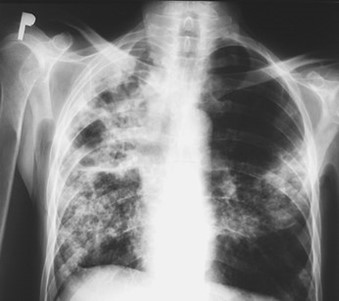

Measles patient with a complication of respiratory failure

Infants, pregnant women, and malnourished children with impaired immune systems are most likely to have complications from measles. The most frequent complication is pneumonia, which can be brought on by a subsequent bacterial infection or the measles virus (Hecht giant cell pneumonia).

Croup, otitis media, and diarrhea from secondary infections are some additional complications. Measles keratoconjunctivitis, which can result in blindness, most frequently affects young children with vitamin A deficiency.